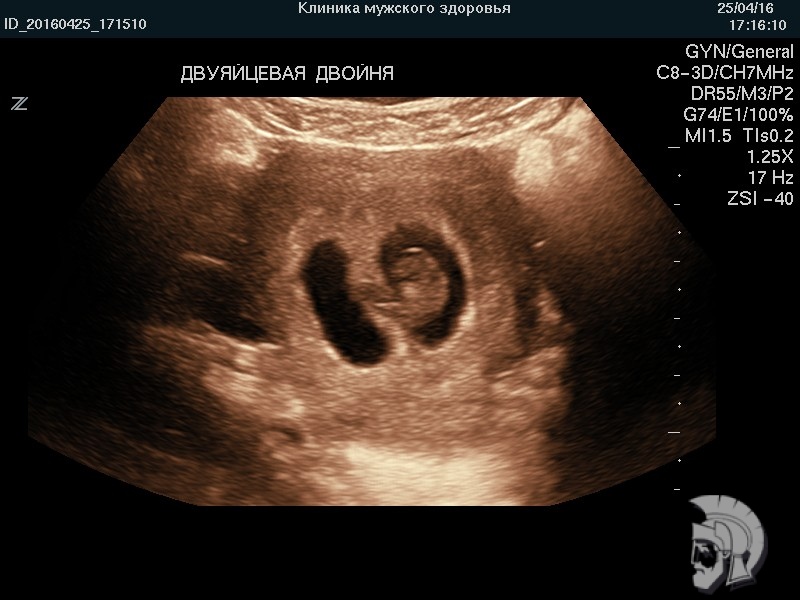

Обратите внимание на совершенное качество фото УЗИ плода, свидетельствующих об экспертном классе аппаратов УЗИ!

Использование ультразвуковых аппаратов экспертного класса с режимами энергетического допплера и цветового ДОППЛЕРа позволяет врачам Курортной клиники мужского здоровья выявить пороки развития плода, маловодие и многоводие, нарушение МППК угрозу прерывания беременности на самых ранних этапах формирования.

| Фото беременности. Двуяйцевая двойня в сроке 7 недель | ![]() |